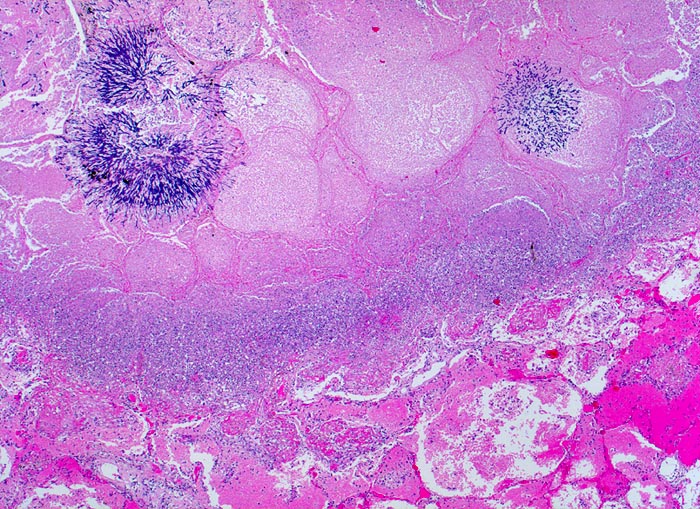

PathoPic – image database / PathoPic ID 4823 - Aspergilluspneumonie

Aspergilluspneumonie

Entzündung infektiös

Lunge

Beschreibung

Seit 14 Monaten bekannte chronische lymphatische Leukämie behandelt mit Chemotherapie. Der Patient entwickelt unter Therapie eine Pneumonie und verstirbt an einer Pilzsepsis.

Histologie

25